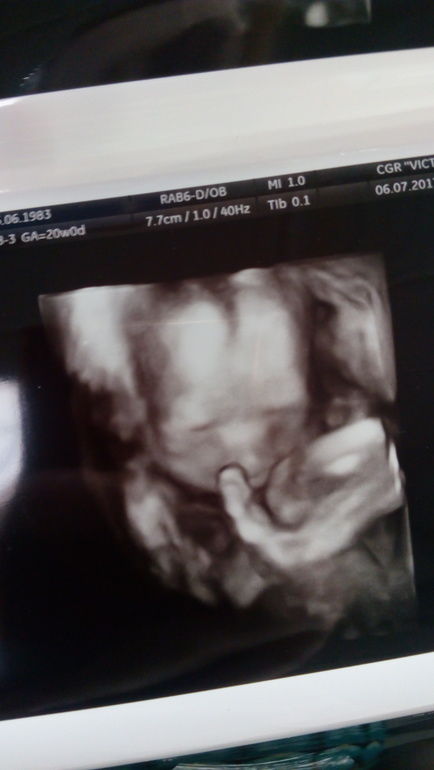

20 недель, экватор ))

Итак, что мы на сегодня имеем 😊

20 недель ровно, половина пути за спиной ✊

Ттт , все отличненько, девулька здоровенькая, растет и развивается😘😘😘

Ее вес уже 370 грамм;